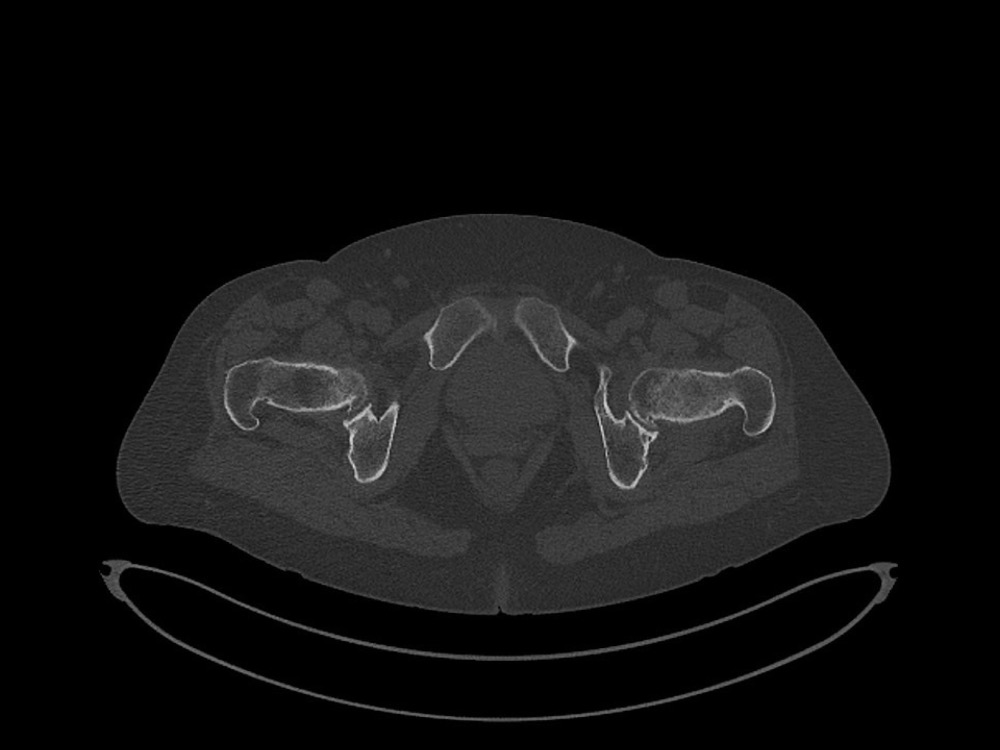

Douleurs de hanche

Linda Ouerd 06/11/2019